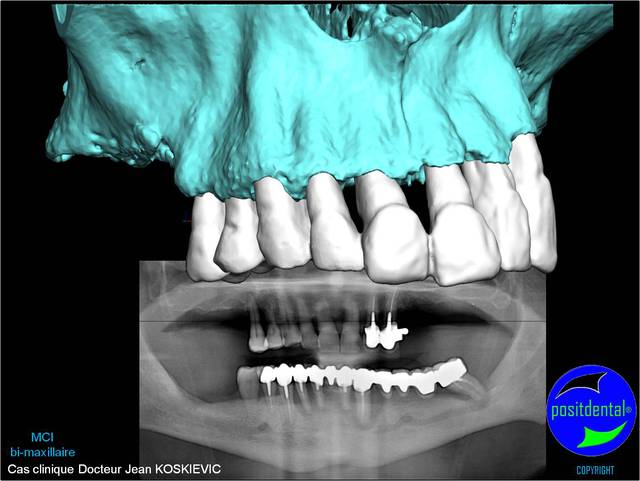

05/05/2011 à 19h19

rendu 3D maxillaire sup, pano et photo